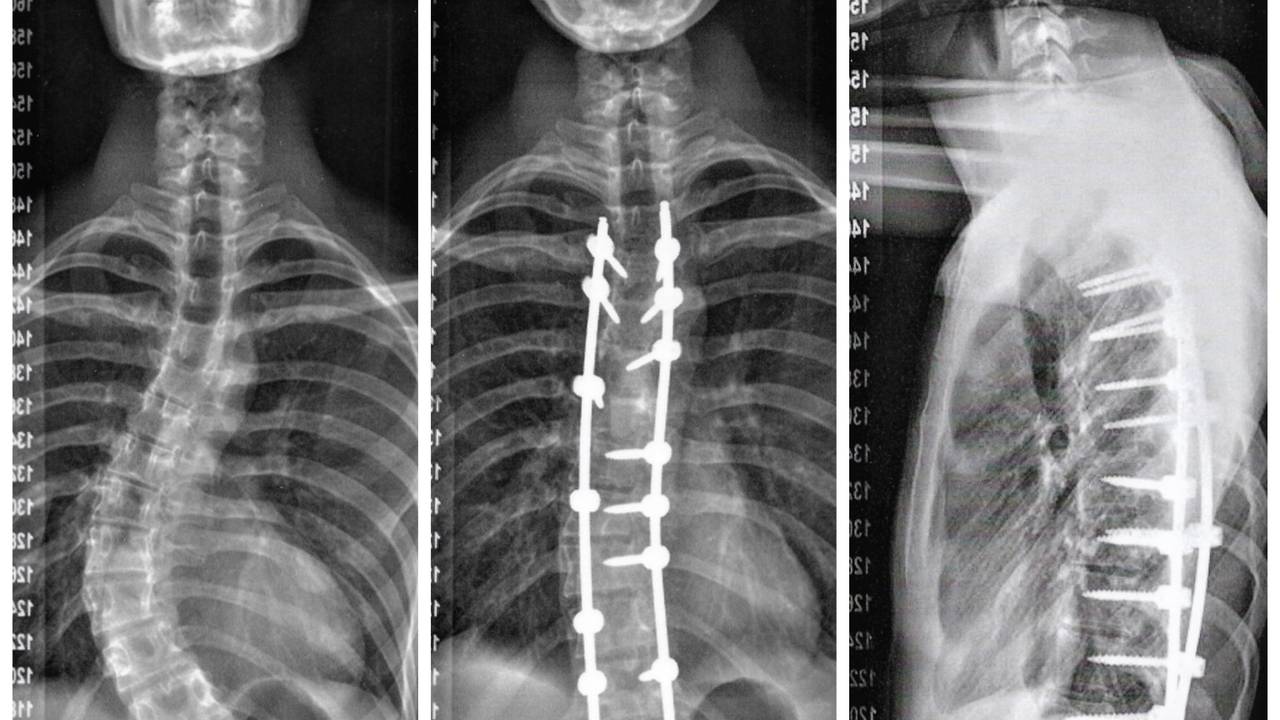

Toen hij vijftien jaar was, schoot Max de lucht in. "Dat was ook het moment dat mijn kromme rug opgemerkt werd door mijn ouders en klasgenoten op school in Oss. Die kromme rug heet scoliose. Het komt best vaak voor, bij drie op de honderd kinderen. Toch hebben maar weinig mensen ervan gehoord" , legt Max uit.

Fysiotherapie, revalidatie, voorkwamen niet dat hij toch onder het mes moest. "Voor een korset was ik te laat. Voor een operatie op mijn 16e te jong. Een jaar geleden ben ik geopereerd in Boxmeer. In de Sint Maartenskliniek zijn ze gespecialiseerd in scoliose. Er zitten nu schroeven en staven in mijn rug en ik heb een litteken van onderkant van mijn nek tot net boven mijn onderbroek als aandenken."

Ondanks dat hij drie liter bloed verloor tijdens de operatie en het afbouwen van morfine behoorlijk pijnlijk was, vindt Max dat de operatie is meegevallen. "Na vier dagen verliet ik het ziekenhuis en na vier maanden begon ik met motorrijlessen. Een wereld ging open. Ik kon eindelijk mijn rug recht houden, daarvoor zakte ik erdoorheen."